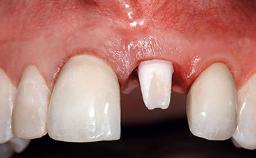

A 32-year-old female Caucasian patient with a compromised maxillary right central incisor was referred to us by a general dentist. Her chief complaints were discomfort and mobility of tooth 11 with unsatisfactory esthetics due to discoloration. The patient reported a previous trauma, some years earlier, as the origin of pathology on the afflicted tooth. Anamnesis was negative for any other dental or periodontal pathology in the remaining dentition. The patient did not take any medication and reported to be a light smoker (5–10 cigs/day). She had high esthetic expectations of her treatment. The extraoral examination revealed a high smile line with full exposure of her maxillary teeth and surrounding soft tissue in the area between the second premolars.

Lip Line No exposure of papillae Exposure of papillae Full exposure of mucosa margin

Periodontal Phenotype Low-scalloped, thick Medium-scalloped, medium-thick High-scalloped, thin

Shape of Tooth Crowns Rectangular Triangular

Soft Tissue Anatomy Intact Defective

Bone Volume Horizontally and vertically sufficient Horizontally deficient Deficient vertically or deficient vertically AND horizontally